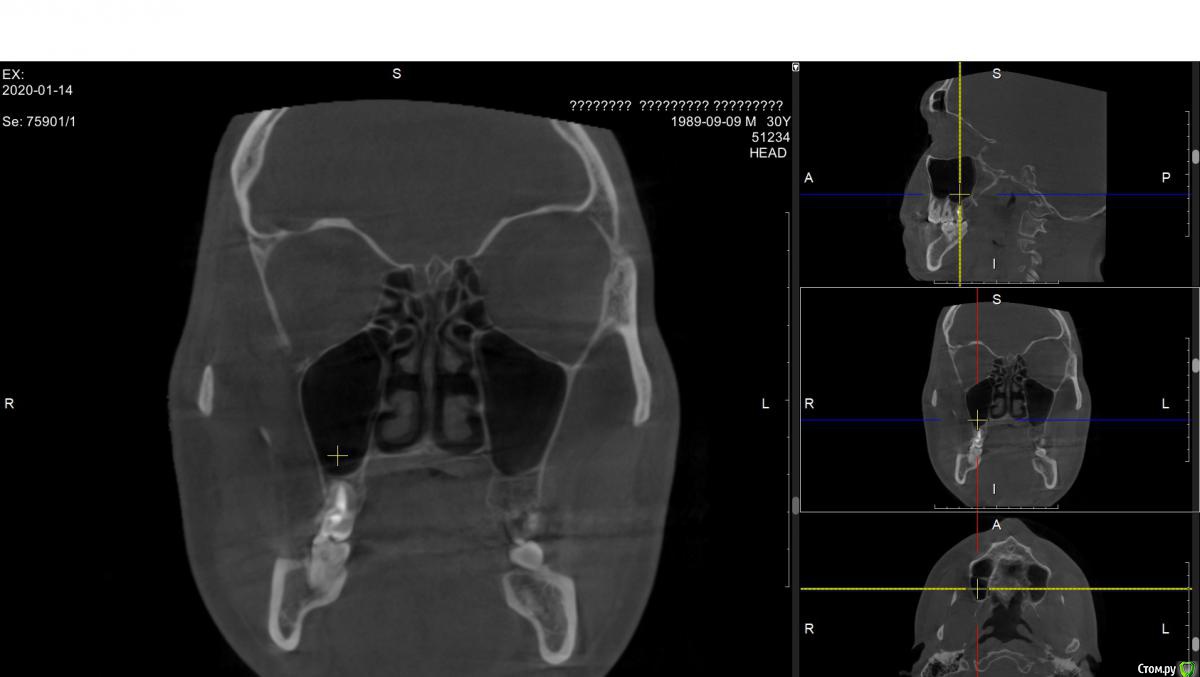

alex889 Опубликовано 8 февраля, 2020 Поделиться Опубликовано 8 февраля, 2020 Подскажите, над предпоследним зубом сверху это инородное тело в гайморовой пазухе? Это могло попасть при лечении каналов зуба мудрости? Может ли такое инородное тело вызывать боли и воспаление в челюстно-лицевой области?Файл КТ: http://fayloobmennik.cloud/7384939 Ссылка на комментарий

wladdX Опубликовано 10 февраля, 2020 Поделиться Опубликовано 10 февраля, 2020 (изменено) Инородных тел не нашёл. То что Вы приняли за инородное тело - перегородка в пазухе Изменено 10 февраля, 2020 пользователем wladdX 1 Ссылка на комментарий